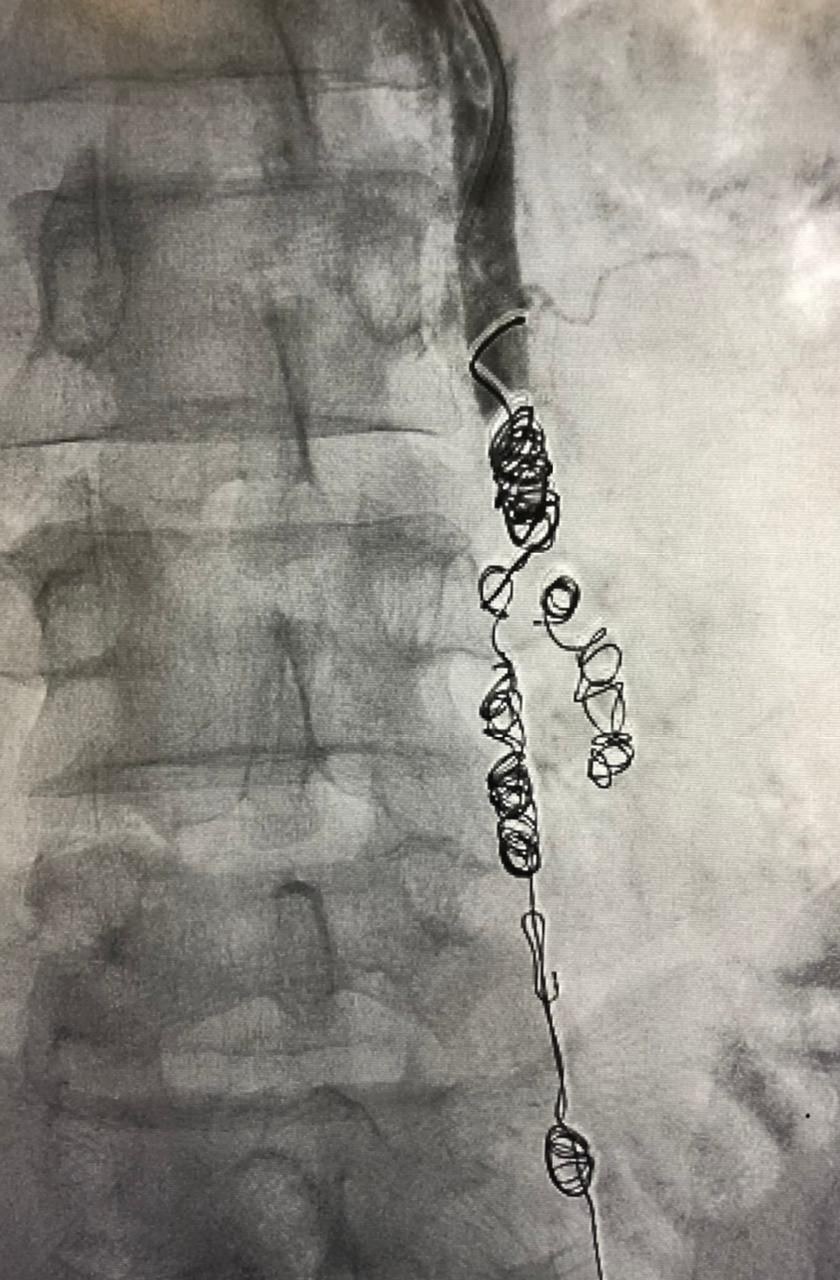

وأوضح رئيس الفريق استشاري الأشعة التداخلية الدكتور محمد شراحيلي أنه تم تحديد واستكشاف جميع الأوردة المسببة لارتجاع الدوالي وتم علاجها باستخدام اللفائف المعدنية الدقيقة وحقن المادة المتصلبة

وأبان أن تقنيات الأشعة التداخلية باستخدام القسطرة تحت استرشاد الأشعة الصوتية و الفلورية من أحدث الطرق العلاجية لدوالي الحوض ،حيث يتوفر العديد من تقنيات العلاج ومنها إغلاق الوريد المتسبب في الدوالي باستخدام اللفائف المعدنية الدقيقة أو من خلال حقن مادة صمغية أو تصلبية  ويتم الوصول لتلك الأوردة من خلال فتحة دقيقة بالجلد لذراع المريض لا تتجاوز الـ 2 ملم، لا تترك علامات جراحية على الجلد